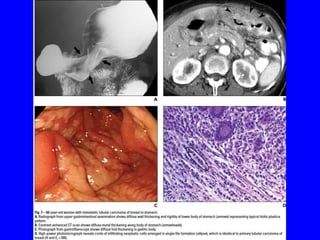

Diagnosis:

• Can be difficult due to an often prolonged tumor-free interval &

benign appearance of the lesions &gastric metastasis may

occasionally mimic a gastric primary.

• Stomach is the most frequent GIT site for metastatic breast cancer.

• The most characteristic endoscopic finding of metastatic lobular

breast carcinoma is a linitis-plastica-like appearance,showing tumor

infiltration along the stomach wall with mural thickening of the

involved segment & submucosal infiltration,makes the diagnosis

difficult on endoscopic & imaging exams.

• Advances in imaging techniques like CT scan &EUS with guided

biopsy have aided confirmation of the diagnosis.